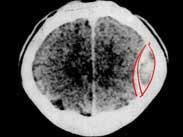

• 硬腦膜下血腫

硬腦膜下出血指硬腦膜與蛛網膜之間的出血,因常易聚積而習慣稱之為硬腦膜下血腫。根據其受傷后出現臨床癥狀和體征的時間不同分為急性、亞急性和慢性三種類型,頭部受傷后3...